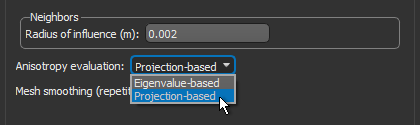

- Select a value between 1 and 3 mm in the Radius of influence edit box.

- Choose Projection-based in the Anisotropy drop-down menu.

- Choose a number of iterations in the Mesh smoothing (repetitions) spin box, optional.